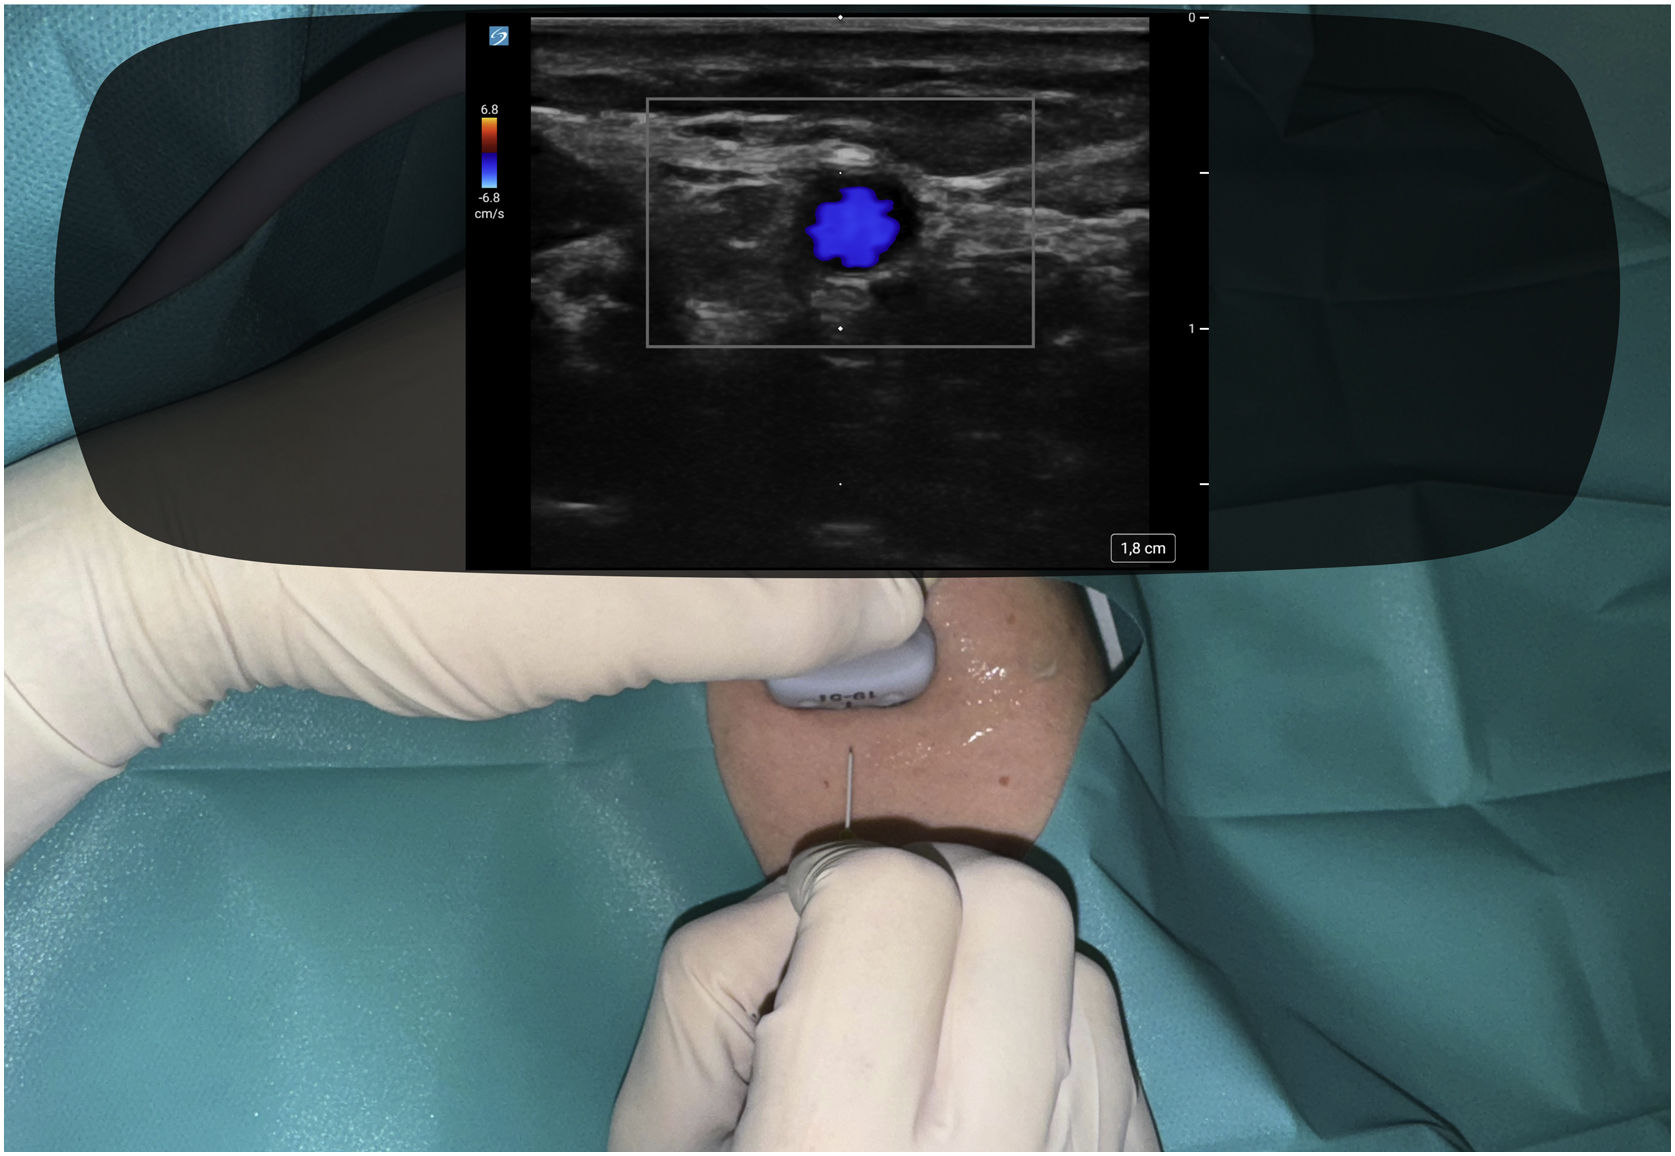

In this context, smart glasses are emerging as a promising tool whose chief advantage would be allowing the operator to maintain the sonographic image and the puncture site in the same field of vision to avoid losing track of the needle, which could contribute to reduce risks and the number of failed attemps while working more ergonomically (Figs. 1 and 2). Since smart glasses are a novel device, there are still few studies on the subject, but the existing evidence suggests that augmented reality glasses could contribute to improving the safety and efficacy of vascular catheterization.3–6

To test this hypothesis, we undertook a study to evaluate ultrasound-guided vascular cannulation with projection of the sonographic images in the lenses of a commercial smart glasses model. The research ethics committee of our hospital considered the study exempt from an ethics review, as it was conducted in a simulation setting. In a preliminary phase, we run several tests to get familiarized with the smart glasses and explore their potential advantages and drawbacks.